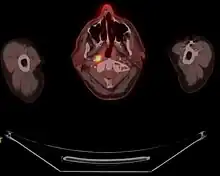

Stage T1 nasopharyngeal cancer

Stage T2 nasopharyngeal cancer

Stage T3 nasopharyngeal cancer

Stage T4 nasopharyngeal cancer